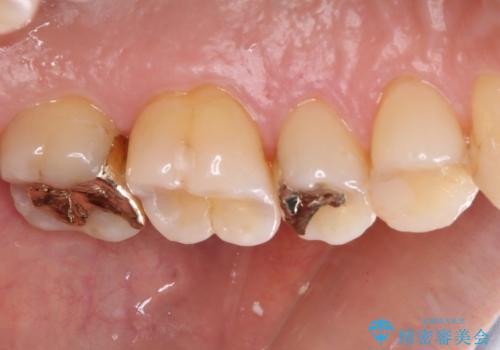

奥歯の銀歯をゴールドでしっかりと治療

- 奥歯の銀歯をすべてゴールドにすることを希望された患者様です。

セラミックインレーによる補綴治療も提案しましたが、ご自身で強い咬合力を認識しており、歯にもインレーにもダメージの少ないゴールドインレーにて処置することとしました。